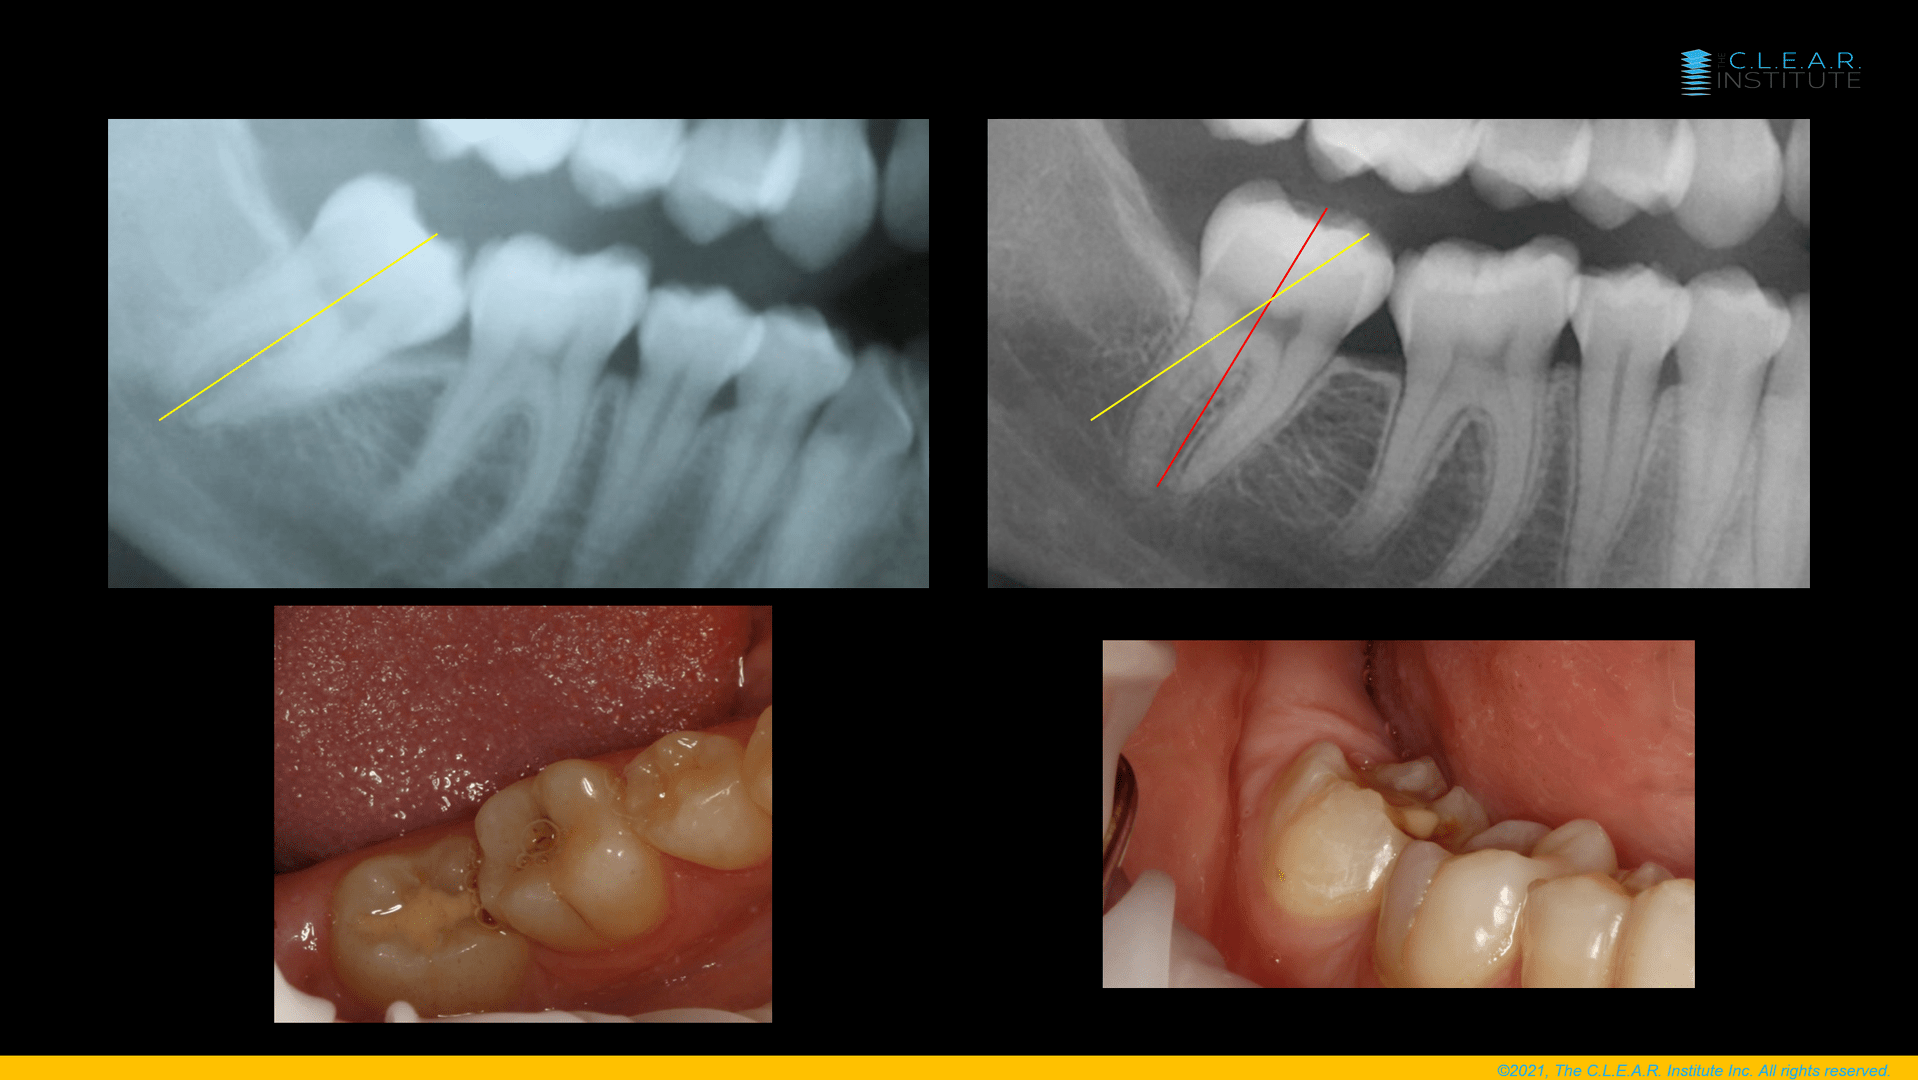

Another example in Figure 3 is how we could upright this second lower molar with clear aligners only. In that case, it was, even more, a root movement than a crown movement. If this can be done with clear aligners, then everything is possible. Sometimes the limits are only your imagination. And of course your knowledge and your confidence.